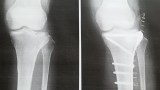

手術は無事終了したのは、骨折日記38にある通り。

入院1ヶ月、リハビリ転院2ヶ月、受傷後そろそろ1年ですが問題多くまだリハビリしてます。まだしゃがめない、階段下り1足では無理、ジャンプも小走りも禁止中。そろそろ抜釘する予定ですが痛みはずーっとあります。

靭帯や軟骨痛めてるんだろーと想像。膝の痛みはプレート抜いたら軽減するかな。イタイの嫌だけど、時期を逃すと大変なので覚悟してます。

プレートを外すと、気持ち的に足が軽くなりますが、もっと痛みもなくなるだろうと思っていたのはそうでもないかなぁとも思います。